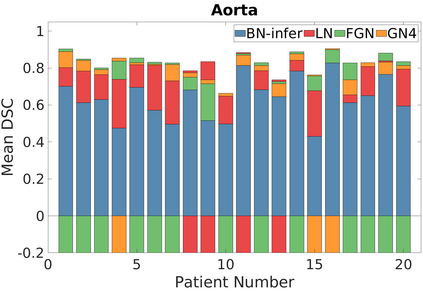

Deep Convolutional Neural Networks (DCNNs) are used extensively in biomedical image segmentation. However, current DCNNs usually use down sampling layers for increasing the receptive field and gaining abstract semantic information. These down sampling layers decrease the spatial dimension of feature maps, which can be detrimental to semantic image segmentation. Atrous convolution is an alternative for the down sampling layer. It increases the receptive field whilst maintains the spatial dimension of feature maps. In this paper, a method for effective atrous rate setting is proposed to achieve the largest and fully-covered receptive field with a minimum number of atrous convolutional layers. Furthermore, different atrous blocks, shortcut connections and normalization methods are explored to select the optimal network structure setting. These lead to a new and full-scale DCNN - Atrous Convolutional Neural Network (ACNN), which incorporates cascaded atrous II-blocks, residual learning and Fine Group Normalization (FGN). Application results of the proposed ACNN to Magnetic Resonance Imaging (MRI) and Computed Tomography (CT) image segmentation demonstrate that the proposed ACNN can achieve comparable segmentation Dice Similarity Coefficients (DSCs) to U-Net, optimized U-Net and hybrid network, but with significantly reduced trainable parameters due to the use of full-scale feature maps and therefore computationally is much more efficient for both the training and inference.